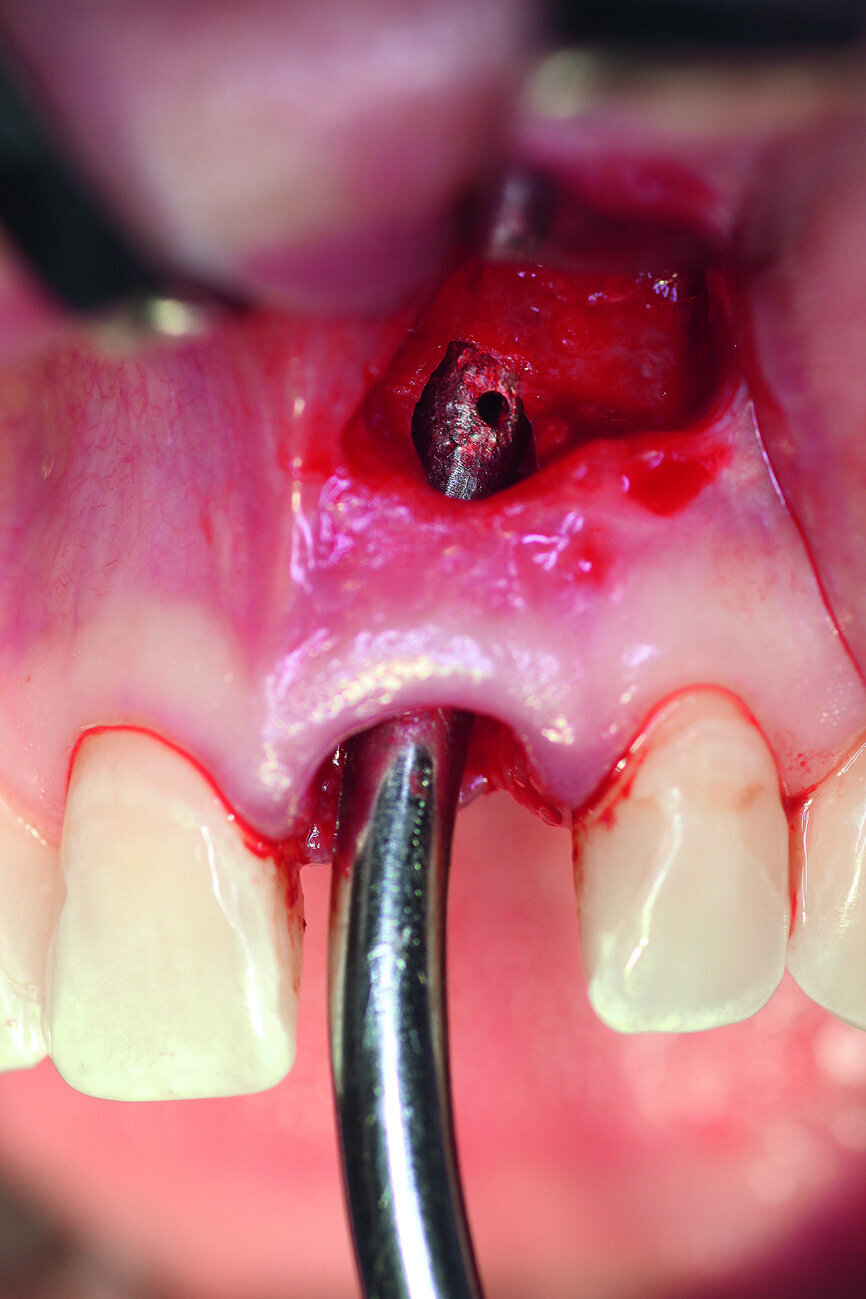

Fig. 4: The implant site was uncovered after five months.

Fig. 5a: A two-piece ceramic implant was inserted.

Fig. 5b: A two-piece ceramic implant was inserted.

After extraction of tooth #21, the apical granulation tissue was excochleated through a semilunar incision (Fig. 3). A two-stage procedure was performed to prevent failure of osseointegration of the ceramic implant and to preserve the soft-tissue structures (papillae and attached gingiva). A claspless prosthesis made from Valplast (Valplast International) served as a temporary restoration. The implant site in region #21 was uncovered after five months (Fig. 4). A two-piece ceramic implant (diameter: 4.2 mm; length: 12.0 mm) was then inserted (Figs. 5a & b). The guidelines for implant placement in the aesthetic zone and the drilling procedure specified by the manufacturer were observed.13, 14 Both vertical and transverse insertion depth are decisive for prosthetic success. The implant can be placed between 1.6 mm and 0.6 mm supracrestally because of a special thermal etching procedure in the collar region; the insertion depth is determined by the gingival height and the existing bone of the adjacent teeth. The implant positioning should be approximately 2–3 mm subgingivally because the abutments are added 1 mm above implant shoulder level. Transversal bone augmentation was performed with a mixture of autogenous bone chips (retrieved from the retromolar mandible), xenograft (Geistlich Bio-Oss, Geistlich Biomaterials) and guided bone regeneration (Jason membrane, botiss biomaterials; Figs. 6a & b). The exposure was performed after four months using a PEEK gingiva former (Fig. 7).